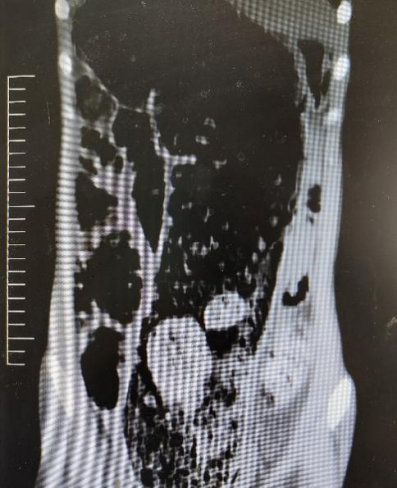

患者李某(化姓)因腹痛初诊于急诊科,经保守对症治疗无效,请普外科协同会诊。普外科科主任权红光教授详细了解患者病史,日常大便不规律,间隔多日大便一次,此次约十余天未解伴明显腹胀。李某多年来曾于外地及徐州多家医院反复就诊,均反应无明显效果。权红光主任根据病史及体征,考虑李某患有成人巨结肠——一种结肠疾病,常因先天性遗传因素引起。收治入院后,行腹部CT检查,提示结肠严重扩张积气积粪,符合成人巨结肠征象。为提升患者生活质量,避免潜在的肠破裂等风险,在权红光主任的指导下,普外科王隽副主任医师带领陈宝鹤、刘阳、宁飞龙及张文卓主治医师等成员为患者实施了手术治疗,为患者带来了新生。